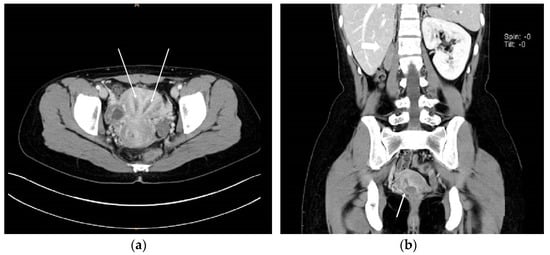

A 23-year-old unmarried woman with no history of coitus came to the Gastroenterology department presenting with acute-onset cramping pain of the left lower abdomen. The patient was referred to the Gynecology department after undergoing an abdominopelvic CT scan, during which one of our radiologists reported “uterus didelphys or bicornuate uterus with left par-ovarian or ovarian cyst” (Figure 1a).

Having been informed that the patient had one kidney, we noticed the patient had HWW syndrome, so we performed a pelvic MRI (Figure 1b)

Pelvic USG and abdominopelvic CT are useful diagnostic tools. Pelvic MRI is strongly recommended as it provides thorough information on the shape of the uterus, vaginal cavity and vaginal septum [6]. In case 1, the obstructed hemi-vagina was more easily identified on MRI than CT images.

Figure 1. (a) Coronal view of abdominopelvic CT image suggesting Herlyn-Werner-Wunderlich syndrome. Uterine didelphys, hematocolpos of obstructed hemi-vagina, and ipsilateral renal agenesis are noted with white arrows.; (b) Coronal view of pelvic MRI T1-weighted image suggesting Herlyn-Werner-Wunderlich syndrome. Uterine didelphys and hematocolpos are noted with white arrows.